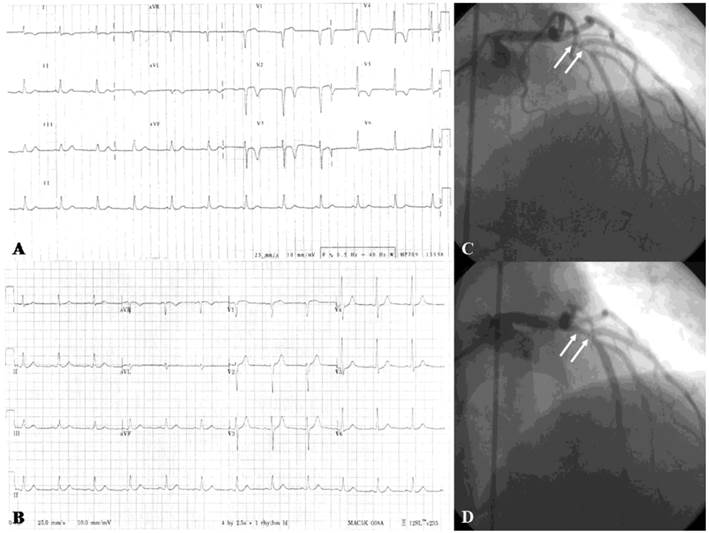

Figure 2

Twelve-lead electrocardiograms and coronary angiograms of variant angina. Chest pain attack (A) and post-sublingual nitroglycerin 0.6 mg (B) Twelve-lead electrocardiograms of a 47-year-old male patient who had variant angina show transient ST-segment elevation in the II, III, and aVF leads. Ten months later he underwent coronary angiography because of recurrent chest pain. The coronary angiograms reveal intracoronary methylergonovine-induced diameter reduction >70% in the mid-portion of right coronary artery (C, arrow), which was relieved after intracoronary nitroglycerin 200 μg administration (D).